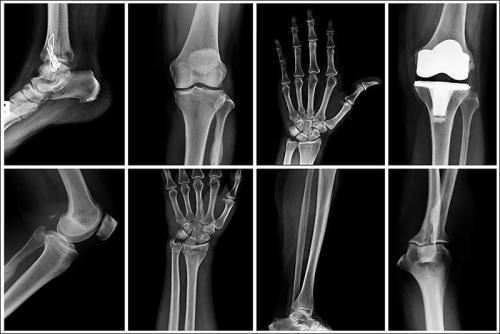

Układ kostno-stawowy